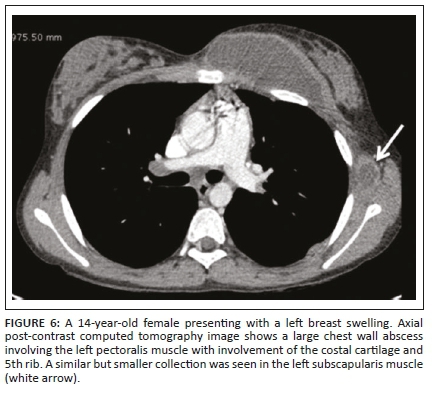

Tubercular involvement of ribs presents as either bony erosions with disruption of the cortical margin or frank destruction, with adjacent abscess formation.6,7 There may be focal expansion of the involved rib with or without periosteal reaction. Tuberculous abscesses of the chest wall can involve the sternum, costochondral junctions, rib shafts, costovertebral joints and the vertebrae.7 They are most frequently found at the margins of the sternum and along the rib shafts. A tuberculous retromammary abscess appears as a focal, smoothly marginated, inhomogeneous, hypodense lesion with a surrounding enhancing rim.13 A direct fistulous communication with the pleura or a destroyed rib fragment found in a tuberculous abscess can be helpful in differentiating it from other types of retromammary abscess.13,14 In the case of chest wall TB, the detection of underlying pleuro-parenchymal disease is often helpful in suggesting the diagnosis.3

Our patients demonstrated similar imaging findings, better documented on CT as lytic destruction or erosion of the sternum, clavicle, acromion, ribs and mandibular condyle. Soft tissue collections were detected around the bony involvement and this was also demonstrated on USG, where accessible. Ultrasonography showed the abscess as a hypo-echoic collection with posterior acoustic enhancement and varying degrees of internal heterogeneity. Some authors have also highlighted the use of USG as a cost-effective and useful modality to assess rib destruction/irregularity and associated soft tissue abscess in chest wall TB.6 In addition, USG provides real-time guidance for obtaining a tissue sample for pathological confirmation. The need for image guidance in accurately obtaining the tissue specimen from deep-seated collections/pathology, which is not appreciated clinically, is an important aspect of management, as the histopathological demonstration of caseous necrosis in the granulomas and microbiological identification in culture provides definite evidence of TB.2